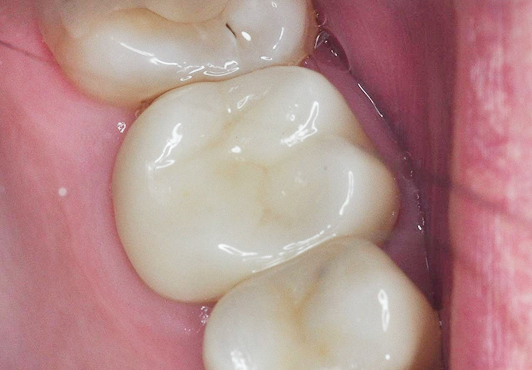

Результат: После проведённого эндодонтического лечения болевые ощущения при жевании устранены, дискомфорт и давление в области гайморовой пазухи исчезли, восстановилось нормальное носовое дыхание. Зуб сохранён, его функция восстановлена. После фиксации коронки полностью восстановлены анатомическая форма и жевательная эффективность, нагрузка распределяется корректно.

Стоматолог-ортопед: Калинин Антон Сергеевич